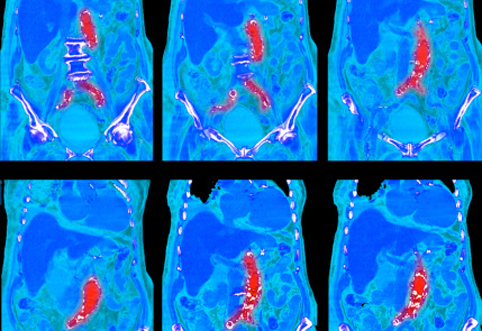

Тактику определяет размер и скорость роста аневризматического выпячивания. При аневризмах диаметром до 5 см возможно динамическое наблюдение с регулярными контрольными обследованиями. Золотой стандарт диагностики — магнитно-резонансная томография (МРТ) или КТ, дополнительно при поражении грудного отдела и не всегда, выполняется ЭХО КГ.